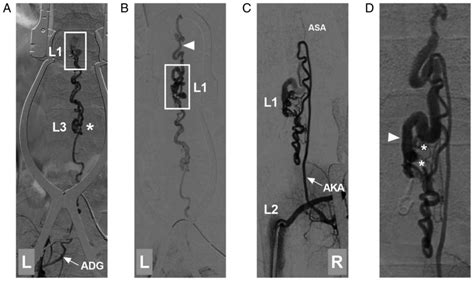

Identifying the Artery of Adamkiewicz prior to surgery is a diagnostic challenge due to its small caliber and variable anatomical path. Computed Tomography Angiography (CTA) has become the gold standard for non-invasive identification. Advanced software allows for multiplanar reconstruction, helping radiologists trace the “hairpin turn” appearance that is characteristic of this vessel as it enters the spinal canal.

• artery of adamkiewicz angiogram

• artery of adamkiewicz dsa

• artery of adamkiewicz ct